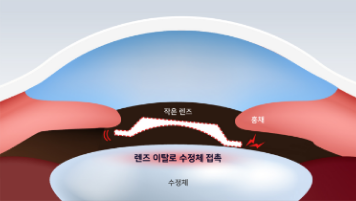

- 기존 난시 ICL

-

렌즈 사이즈로 볼팅을 높여서 회전 가능한 공간을 줄입니다.

이는 눈 속에 렌즈가 끼어 회전을 못하도록 하는 방법으로

시간이 지난 후 안구 내 안압 상승 및 녹내장의

부작용이 발생할 수 있습니다.

딱 맞는 크기의 렌즈

수평으로 렌즈를 삽입할 경우 렌즈 움직임을 최소화하기 위해 눈 보다 큰 사이즈의 렌즈를 삽입하게 되는데 이는 안압 상승의 문제점과 백내장과 녹내장과 같은 치명적인 부작용이 발생할 수 있습니다.

작은 렌즈를 삽입할 경우

-

딱 맞는 크기의 렌즈

-

큰 렌즈를 삽입할 경우